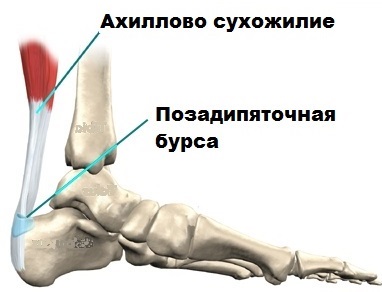

Тендинит Ахиллова сухожилия: симптомы и лечение

Раздел: Картинки на заметку